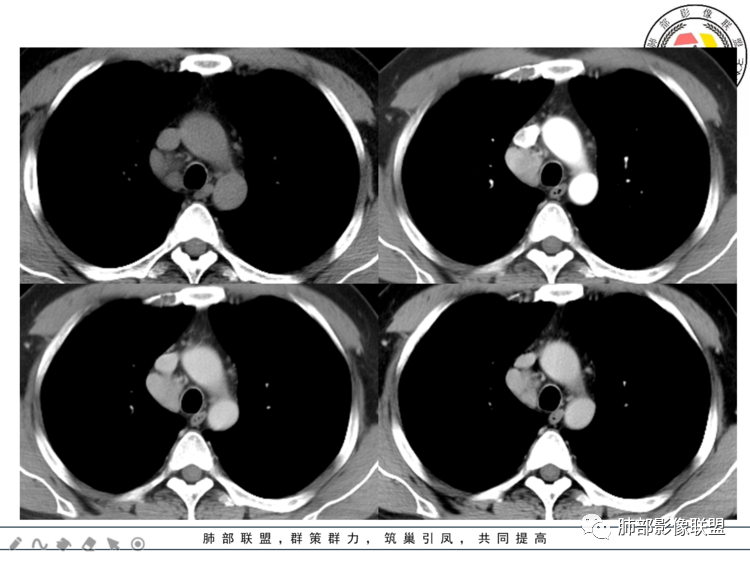

3.1单发型CD的肺部表现

单发型CD多为透明血管型,所以明显强化和中央分枝状钙化具有特征性。在CT上表现圆形或类圆形软组织密度影,伴或不伴周围淋巴结增生,体积一般较大,边缘光整,病灶中央的弧形、线样、分枝样及枯枝样钙化(因为肿块内增生的血管组织玻璃样变或退变后钙盐沉积,故多呈血管样铸型的分支状或枯枝状);透明血管型因为其内血供丰富,周围可见粗大的供血动脉,在多期扫描动脉早期明显强化,强化程度与大血管相仿,又由于病灶内血管壁玻璃样变或纤维化及内皮细胞过度增生致血管腔狭窄,对比剂退出减慢,故延迟扫描扫描仍可持续强化,呈“早进晚出”的强化方式。因为其血供丰富,坏死、囊变或出血少见,但是有时候病灶内灶状或条片状低密度影,是纤维组织或发生玻璃样变性的血管结构,而不是缺血坏死区。

40岁,男性。右中上纵隔见实性团状软组织影,密度均匀,边界光整清晰,与周围结构分界清晰,增强后动脉期明显均匀强化,静脉期延迟期强化逐渐减低。定性:良性病变或肿瘤,常规考虑巨淋巴结增生CD,需鉴别诊断的疾病有1神经源性肿瘤如神经鞘瘤,沿纵轴生长,横轴大于纵轴,但一般有AB区,有囊变坏死,多见后纵隔,强化渐进性强化,发生前中纵隔的恶性程度高,此例不太支持,但不排除;副神经节瘤,囊变多见,不支持;节细胞瘤,一般纵轴大于横轴,不支持;2神经纤维瘤SFT,蛇蚊征,待排,3孤立性转移瘤,少见,一般有原发肿瘤病史,肿瘤标志物异常,环形强化,不支持。4淋巴瘤,常多发淋巴结肿大,少见囊变坏死,待排。5异位甲状腺,一般平扫密度较高,此例不支持。

患者中年男性,体检发现纵隔占位。胸部CT:右上前纵隔不规则占位灶,位于上腔静脉后方,血管无推移,边缘光滑,密度均匀,增强动脉期明显强化,综合考虑良性病变,巨大淋巴结增生症可能大。鉴别神经源性肿瘤。

中纵隔内类椭圆形软组织占位,密度均匀,边界清晰,与周围结构分界清晰,腔静脉向外推移,周围见数个增大淋巴结,增强扫描明显均匀性强化,考虑良性,CD可能性大,鉴别神经源性肿瘤。